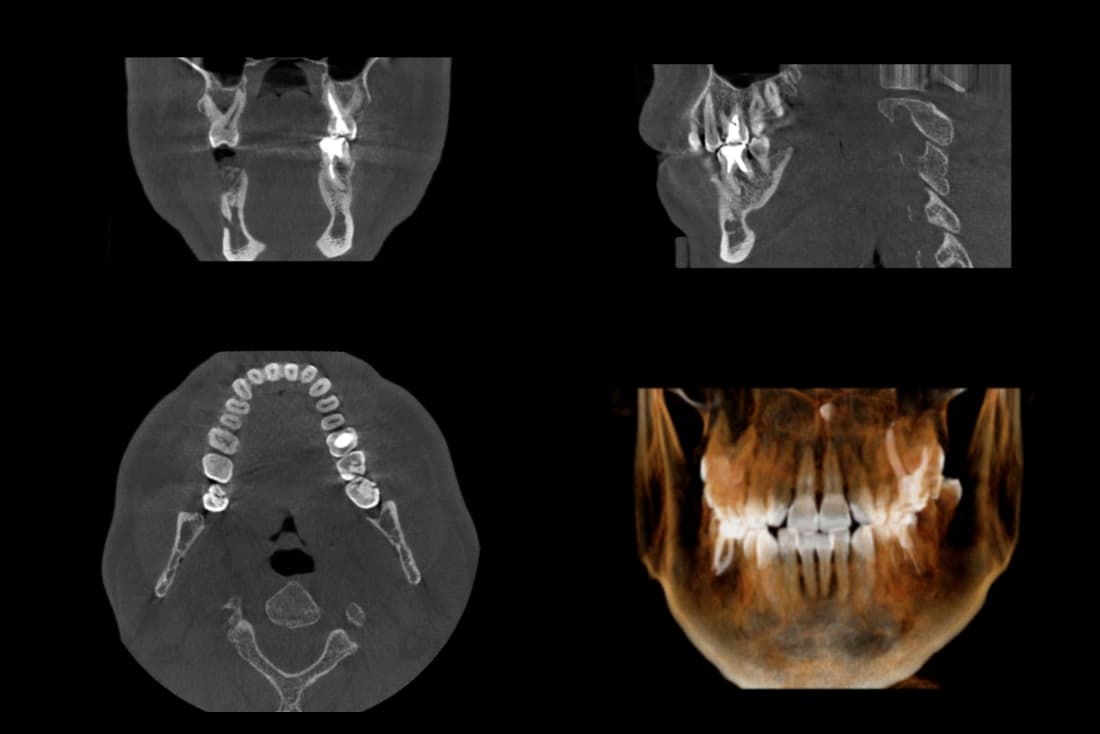

We have a private operation room, dental units with automatic cleaning system, high quality three dimensional CBCT, Er-YAG laser and ultrasonic instruments to realize high success rate of treatments.